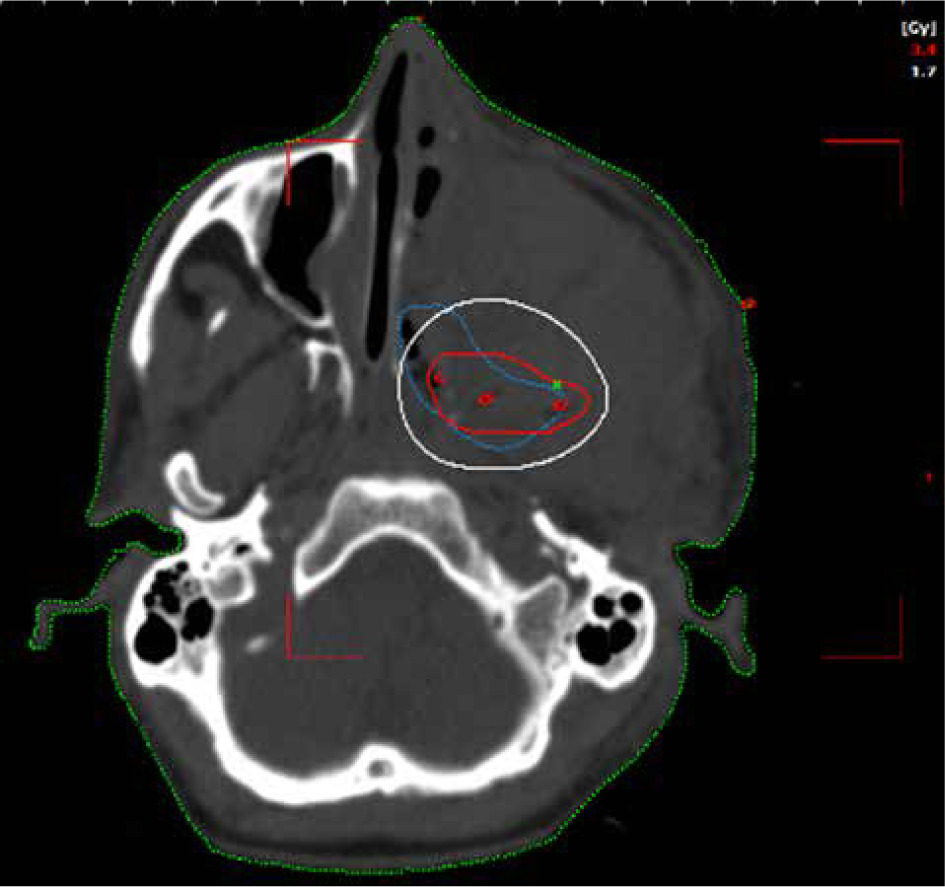

Planning CT was performed on Philips Medical System Cleveland with 3 mm slice thickness encompassing tumor bed, implanted catheters, and a 5 cm cranio-caudal margin. Target volume was considered gross residual tumor, based on the clinician’s assessment, aided in location by bony landmarks, such as pterygomaxillary fissure, temporal process of the zygomatic bone, greater wing of the sphenoid, occipital condyle, and the lateral nasal wall on the opposite side. High-risk clinical target volume (HR-CTV) was generated from the residual volume with a 3 mm margin, and edited based on patterns of spread. The American Brachytherapy Society recommends a CTV based on clinical parameters. In EBRT, a margin of 5 mm is recommended. Due to the proximity of critical neural tissue and in anticipation of high doses close to the implanted catheters, the margin was limited to 3 mm in this case.

A dose of 27.2 Gy in 8 fractions, corresponding to 3.4 Gy per fraction was prescribed to HR-CTV. Sagi-Nova brachytherapy planning system was applied to generate the plan, and dose distribution was optimized by forward planning altering geographical dwell positions if required to ensure adequate coverage of HR-CTV (Figures 2 and 3), while maintaining organs at risk (OARs) constraints to the eye, optic nerve, and chiasma. CT simulation was repeated daily for catheter displacement or positional changes. Images were satisfactory throughout the treatment and no changes were made. The sagittal and axial views of the plan are shown in Figures 2 and 3.